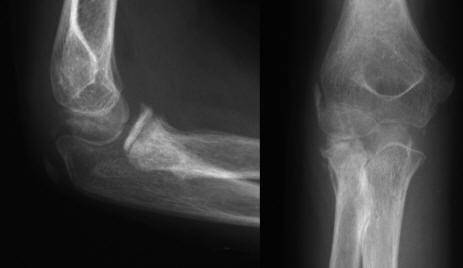

X线片

虽然桡骨颈有高达 12 度的外翻角,但是桡骨头应该在每个角度均指向肱骨小头,在桡骨干与肱骨小头的中心连线上。